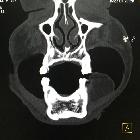

CT

Classic appearances are of a superficial circumscribed, low attenuation mass (typically approximately -65 to -120 HU) with minimal internal soft-tissue component. Again, areas of calcification may be present although are more frequently associated with well-differentiated liposarcoma .

Deeper or larger lesions may have scattered areas of internal soft-tissue density, often more apparent on CT versus MRI. These may represent areas of fat necrosis, fibrous tissue, blood vessels, or muscle fibers; these lesions cannot be confidently differentiated from liposarcoma by imaging.

Intramuscular lipomas may invade and interdigitate with the associated skeletal muscle, resulting in a characteristic striated appearance which may help distinguish from liposarcoma .